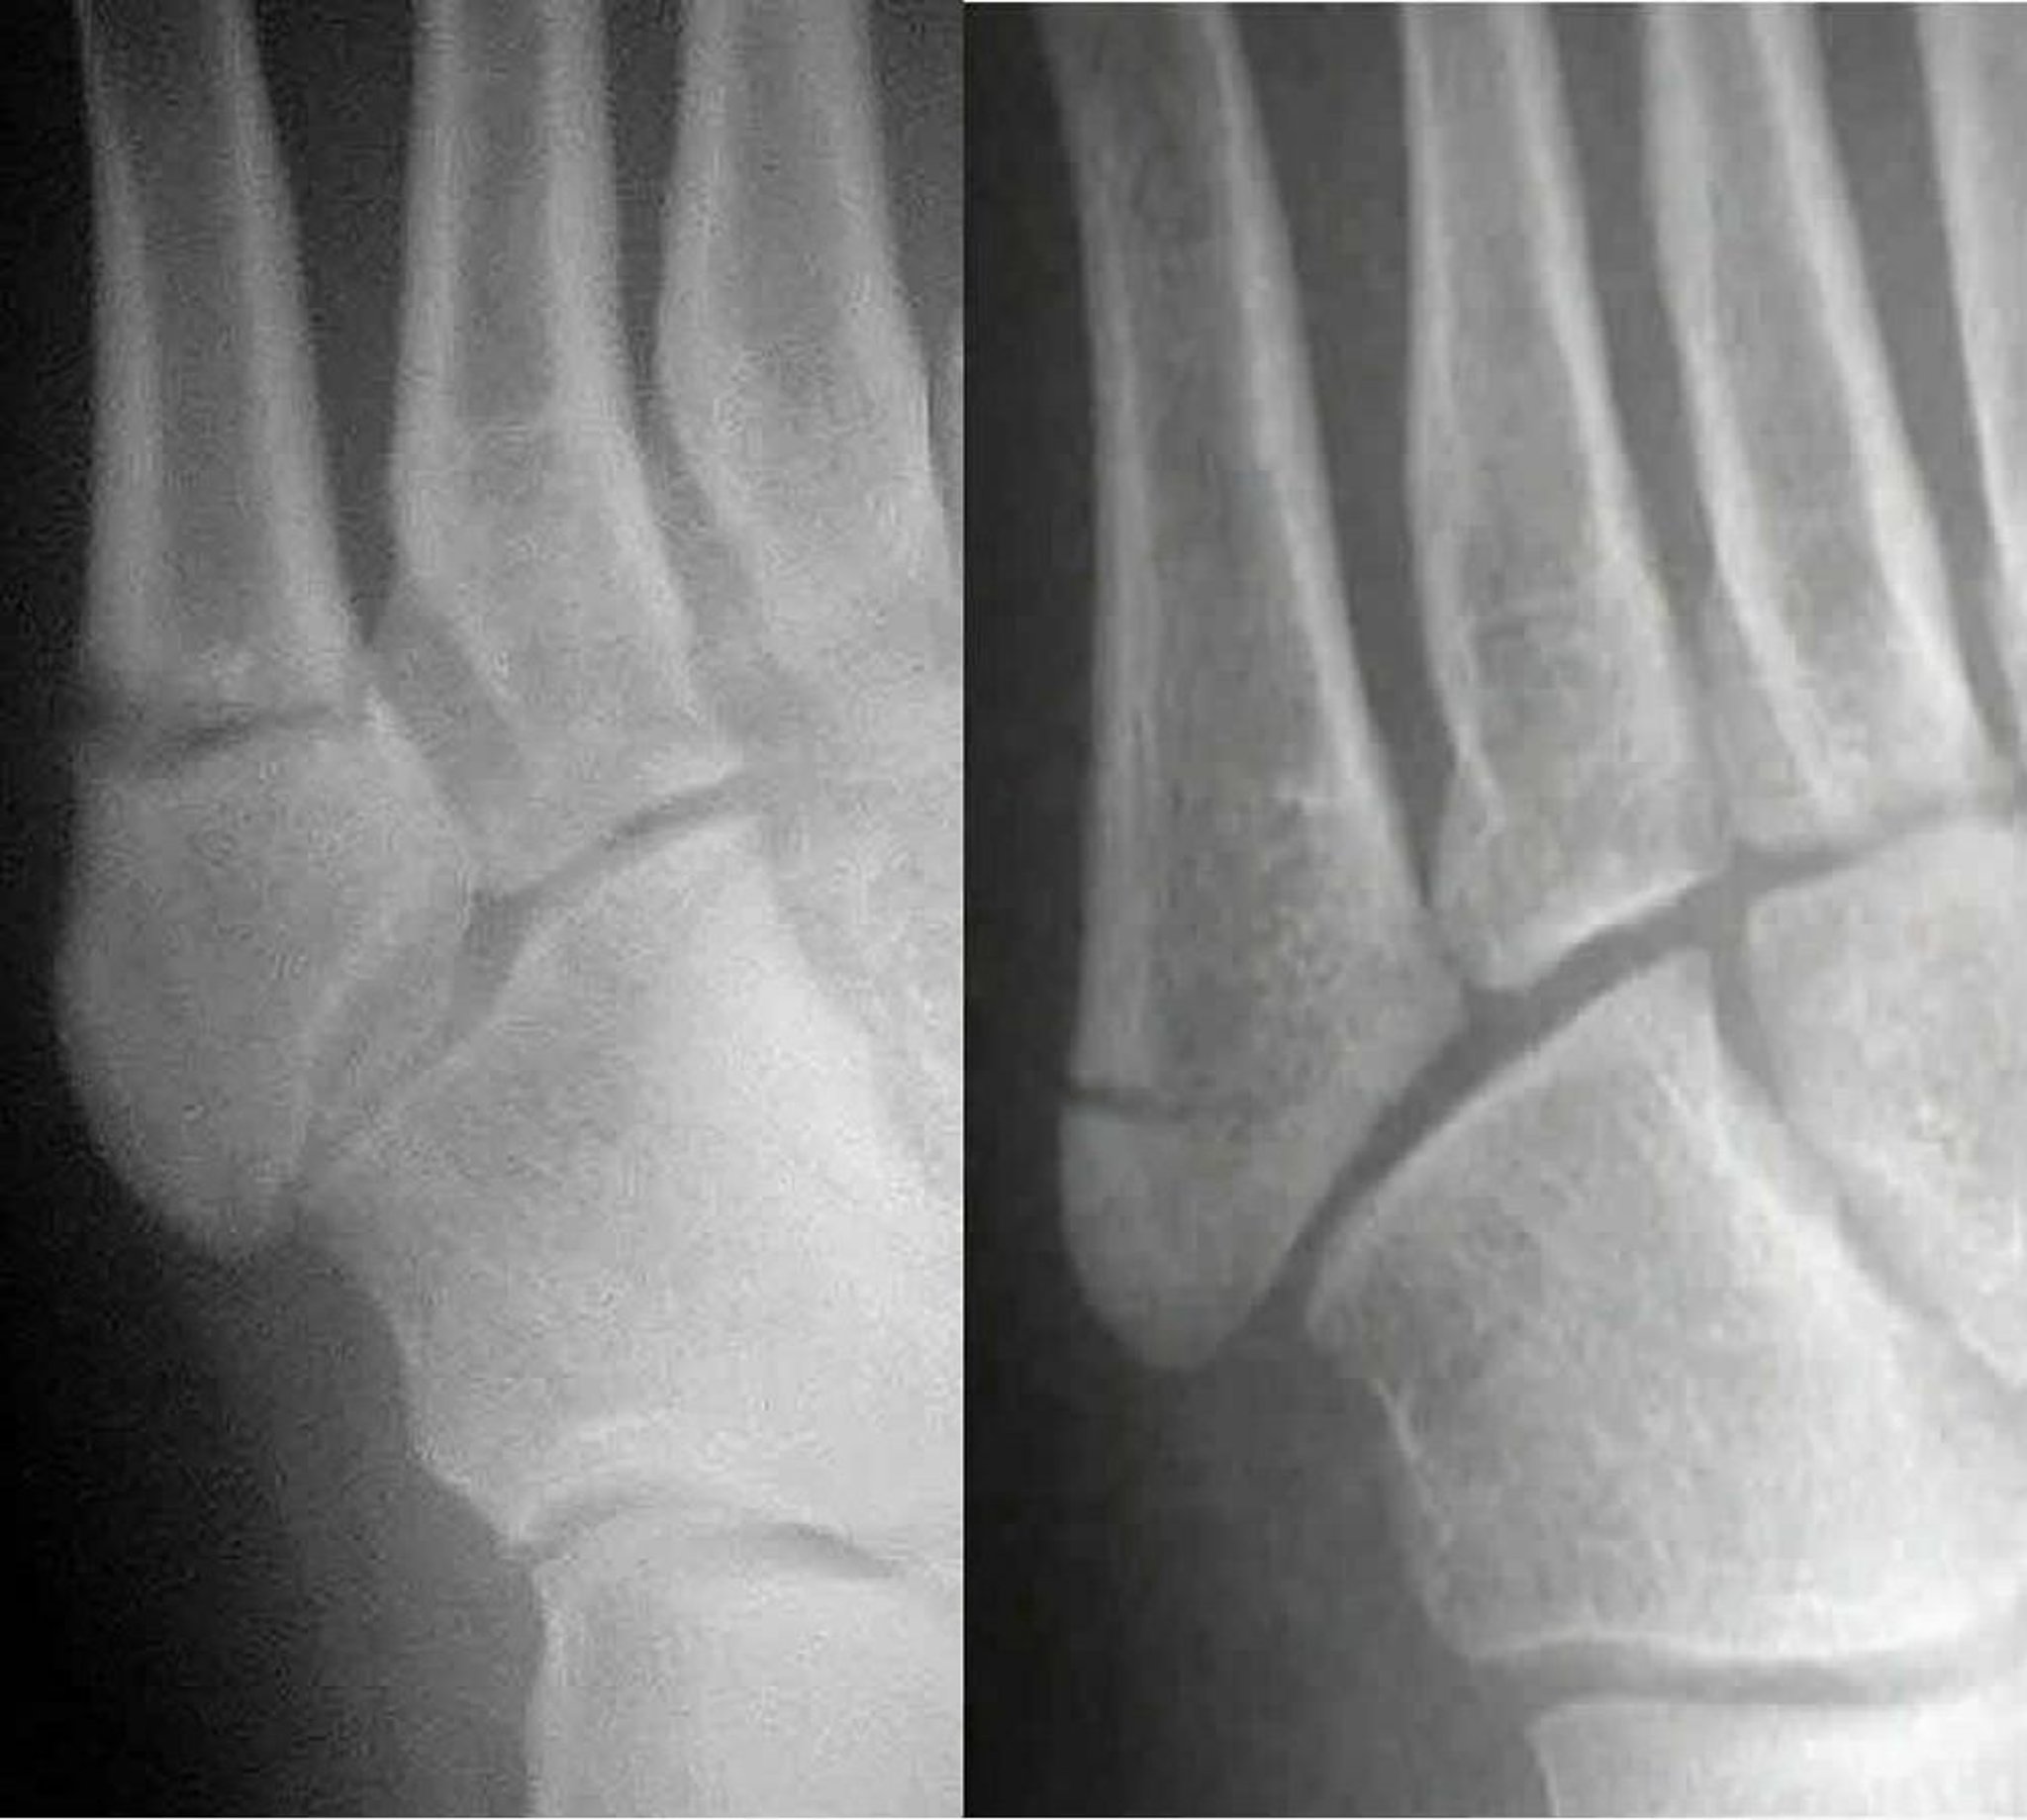

Fratture di Jones versus pseudo-Jones

La frattura di Jones (a sinistra) interessa la diafisi del 5o metatarso; una frattura pseudo-Jones (a destra) interessa la base del 5o metatarso. Distinguere i due è importante perché vengono trattati in modo diverso.

Images courtesy of Danielle Campagne, MD.